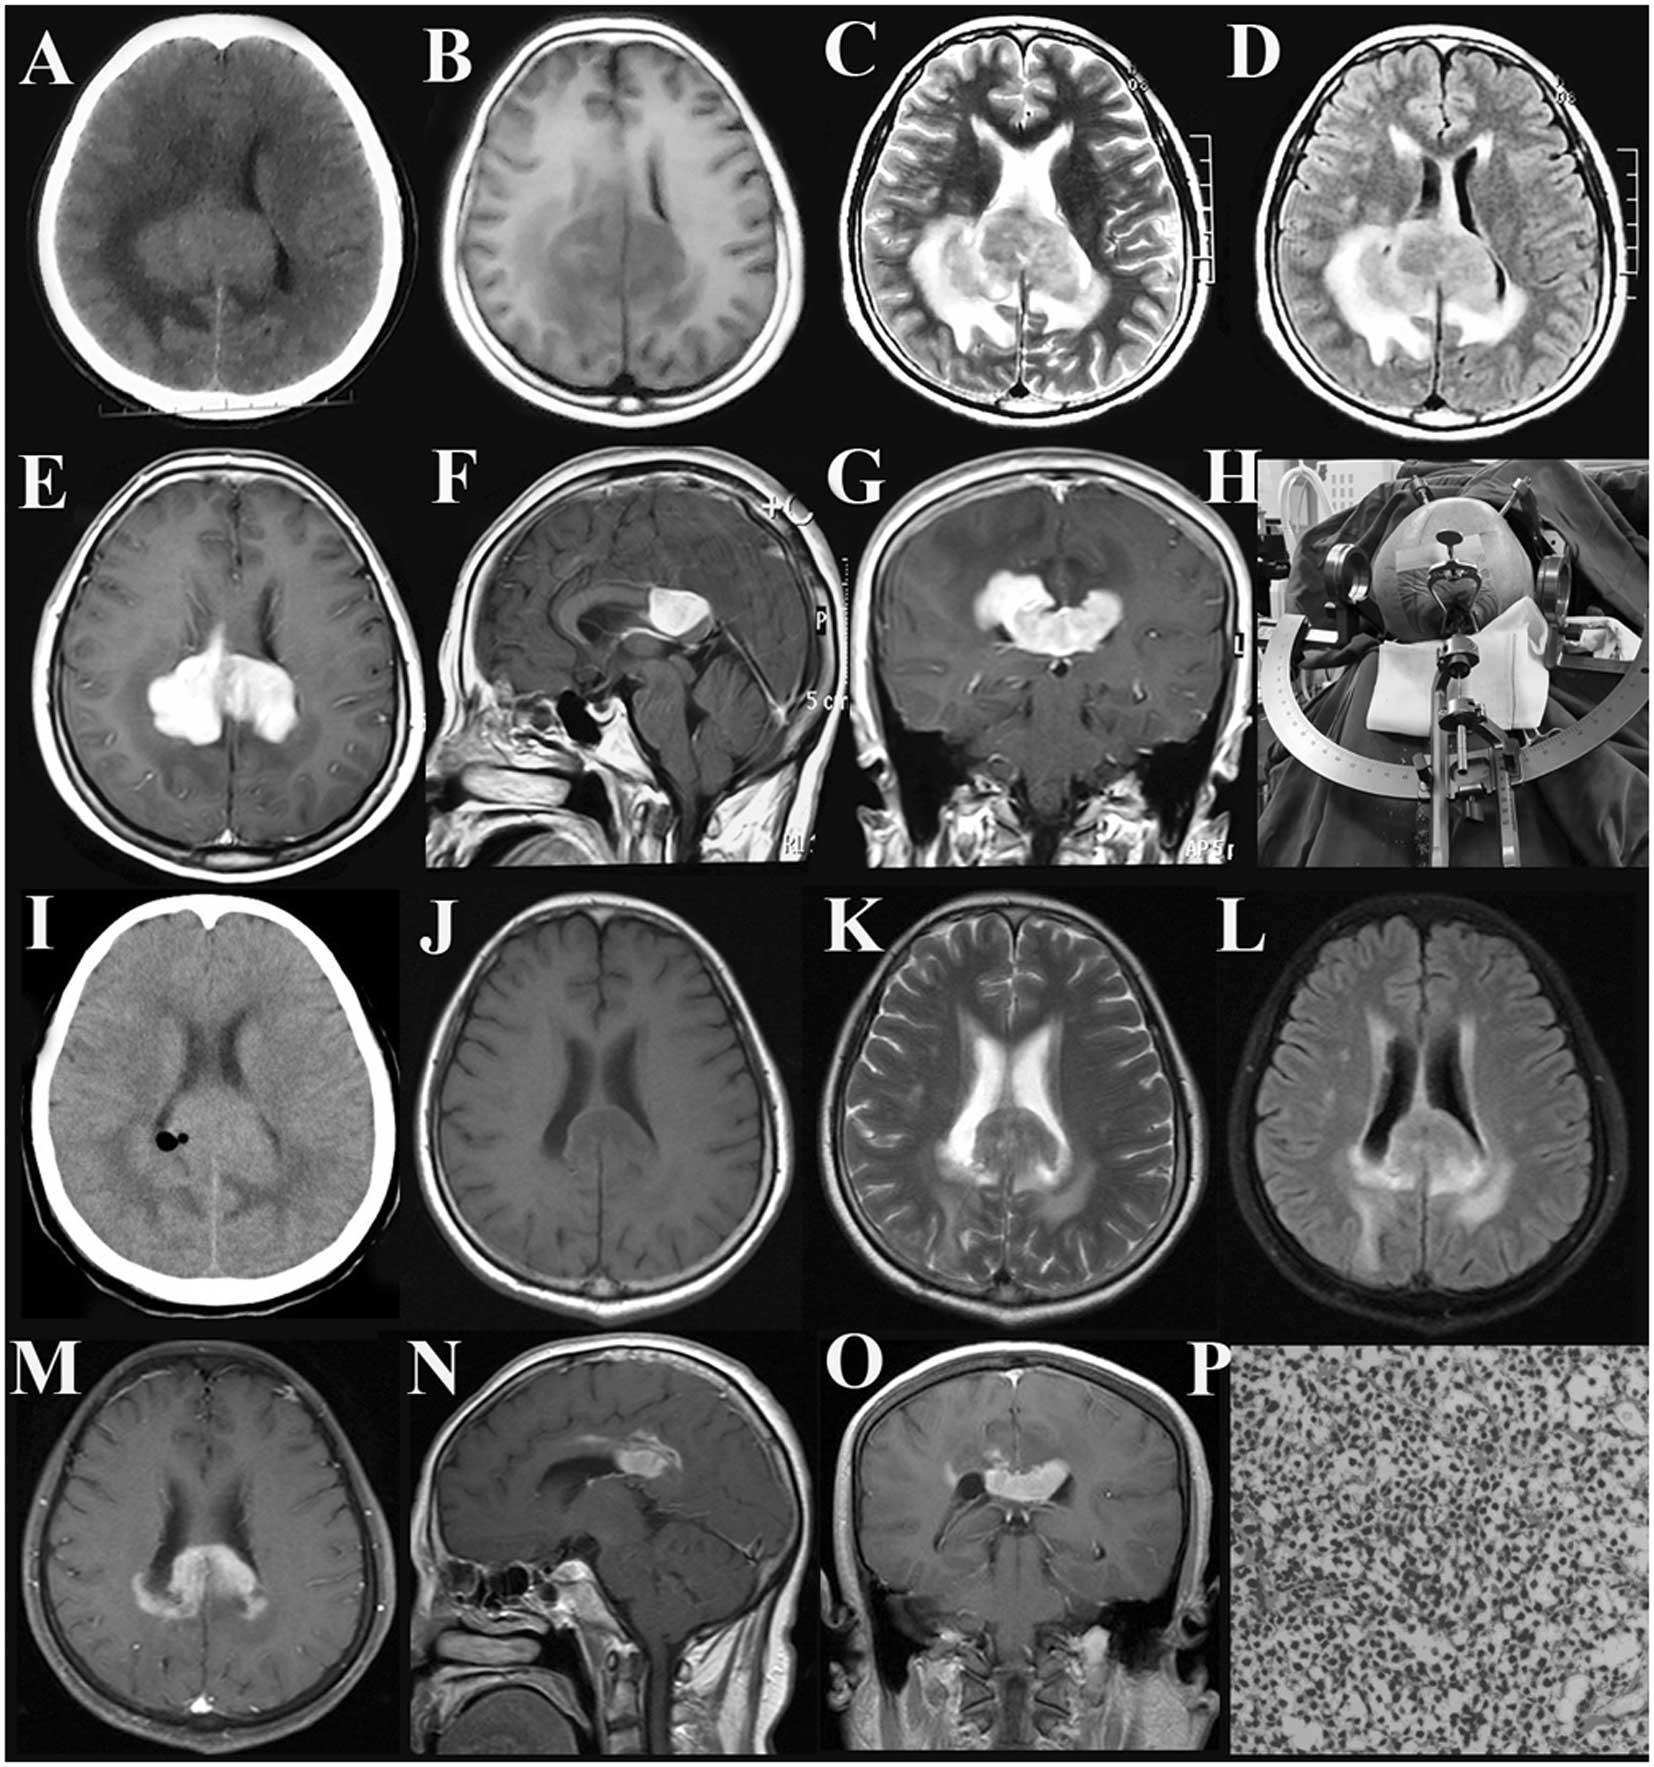

Fazekas grades. Фазекас 2 мрт. Кт мозга. Геморрагическое пропитывание мозга на кт. Токсическое поражение мозга кт.

Fazekas grades. Фазекас 2 мрт. Кт мозга. Геморрагическое пропитывание мозга на кт. Токсическое поражение мозга кт.